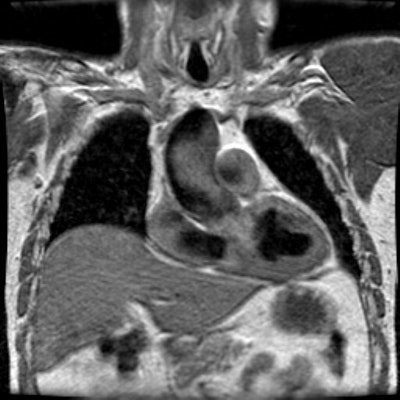

Post stenotic aortic dilatation

There is dilatation of the ascending aorta shown on the MR images below. The sinotubular junction is not affected. Flow void within the ascending aorta on flow images is related to turbulent flow associated with the stenotic aortic valve. The patient also has a coartation of the descending aorta. Turbulent flow void can be seen at the site of coarctation. About 50% of patients with aortic coarctation have a bicuspid aortic valve which can prematurely degenerate.